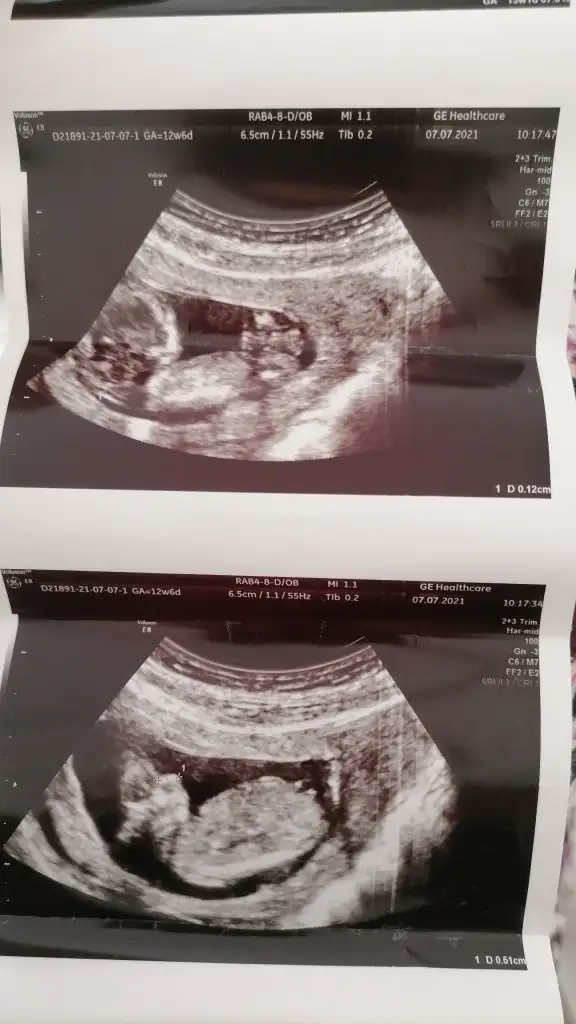

Alttaki kesin kız gibi üsteki emin olamadım ama sanki erkek gibi sankiEki Görüntüle 2884621 Eki Görüntüle 2884622Ikra meyra bunlar da benim ikizlerimin 12 haftalık görüntüsü, yorumlarsan sevinirim